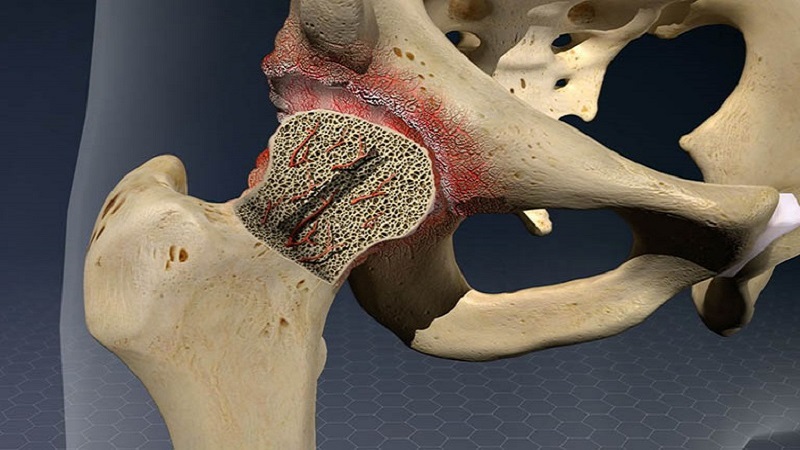

Hoại tử xương xảy ra chủ yếu do khi sang chấn, hệ mạch máu bị thương tổn và không thể nuôi dưỡng một hoặc nhiều phần xương gãy. Bạn có thể bắt gặp hiện tượng này ở một số dạng gãy xương kín như: Gãy di lệch cổ xương đùi, gãy xương thuyền, gãy cổ xương sên,...

Một số dạng gãy xương có thể gây sang chấn lên mặt chịu lực của khớp, điều này dẫn đến hiện tượng lệch vẹo trục xương, tổn thương sụn khớp và kéo theo tình trạng thoái hóa khớp. Nếu sang chấn diễn ra ở một vài xương nhỏ và ngắn, thoái hóa khớp có thể ít gây ảnh hưởng đến sinh hoạt hằng ngày. Tuy nhiên khi gãy xương xảy ra ở khớp vai, khuỷu tay hay khớp háng, khớp gối thì vấn đề sẽ nghiêm trọng hơn rất nhiều.